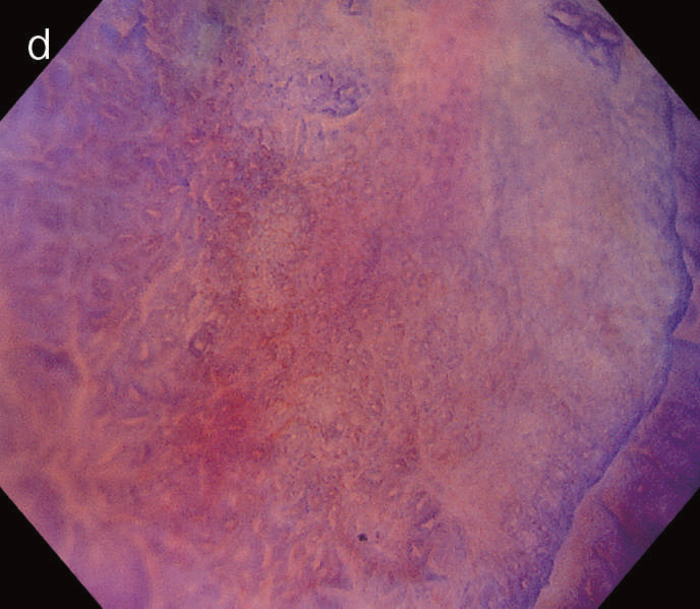

図5 UC関連粘膜下層浸潤癌の内視鏡所見

- 白色光像:直腸(直腸S状部)の発赤調変化。背景粘膜は寛解期にあった。

- 色素内視鏡像:病変辺縁が明瞭となるが,病変肛門側で不明瞭であった。

- NBI拡大像:口径不同,不均一な微小血管と不整な表面構造所見を認めた。

- pit pattern像:小型の類円形,管状pitを認めた。